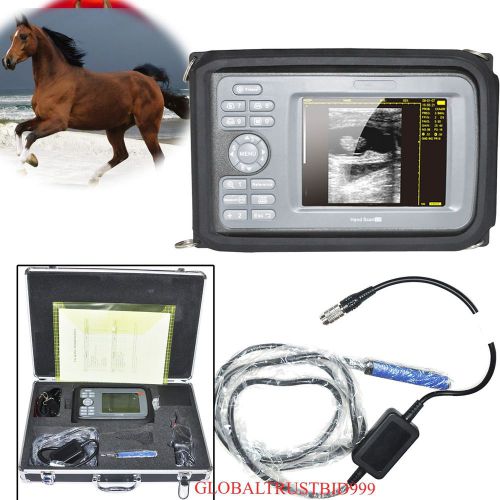

AA Veterinary Digital PalmSmart ultrasound scanner for large animal rectal probe

HOT VET Veterinary Digital Ultrasound Scanner Machine+7.5mhz Rectal Linear probe

Veterinary Wrist Handheld portble Ultrasound Scanner Machine w waterproof Probe

Hot Promotion Palmsmart VET Veterinary ultrasound scanner 6.5MHZ Rectal probe